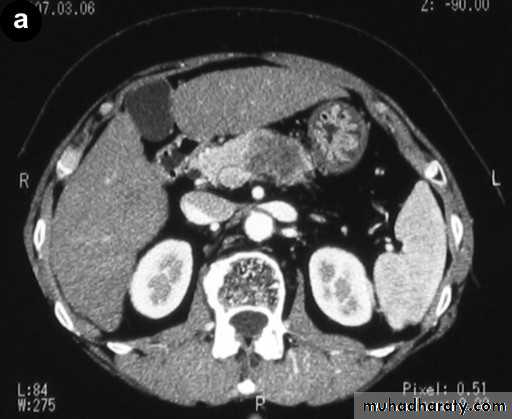

Pancreatic adenocarcinoma

It locate in head of pancreas in 2/3 cases.It obstruct CBD even with small lesions giving rise to jaundice.

Tumors in the body or tail become large until giving rise to symptoms.

The important sign of carcinoma at both CT and US is a focal mass within or deforming the outline of the gland.

On contrast-enhanced CT, the tumor appears of lower density compared to the normal pancreatic tissue. The main pancreatic duct may be dilated distal to an obstructing mass . Most tumors are irresectable at time of diagnosis because of involvement of regional LAP, liver metastases and regional vascular encasement.